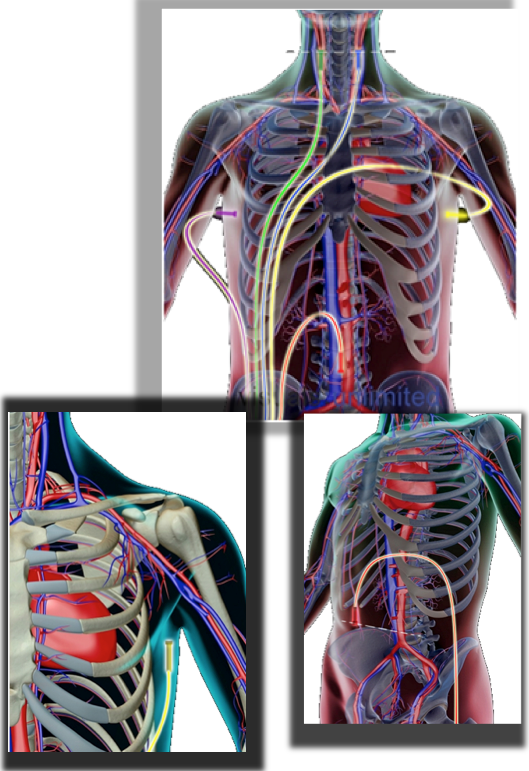

The Analyzer ANESA has five sensors, which are to be placed onto so-called biologically active points of patients’ body.

Bioactive or so-called reference-points used during examination, are:

· Bifurcation of the right and left neck artery (two points)

· Right and left armpit (two points)

· Umbilical area (one point)